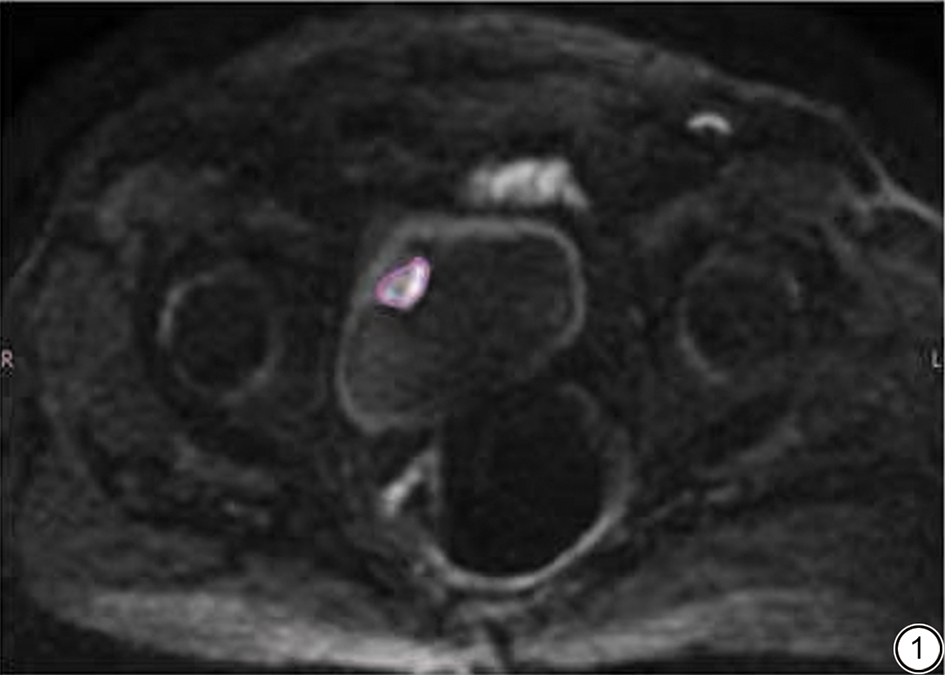

采用ADW 4.6后处理工作站中的mADC后处理软件进行图像后处理。分别由两名具有十年以上工作经验的放射科主治医师参考T2WI、DWI序列在IVIM-DWI图像上手动选取膀胱肿瘤ROI,在肿瘤显示的最大层面上进行,尽量避开肿瘤囊变、坏死、液化区域,避开膀胱壁,避开肿瘤与膀胱壁交界区域,并尽可能使ROI范围显示为最大,由一名具有三十年以上工作经验的放射科副主任医师解决相关争议问题并确定最终的ROI范围。每位患者的膀胱肿瘤病灶均选取3个ROI,通过mADC后处理软件分别得出图像分析数据:表观扩散系数(apparent diffusion coefficient, ADC)、真实扩散系数(D值)、灌注分数(f值)以及灌注相关扩散系数(D*值),对这3个ROI的ADC值、f值、D值、D*值分别取平均值。ROI勾画见图1

图1  感兴趣区勾画示意图。

Fig. 1  Schematic diagram of region of interest delineation.